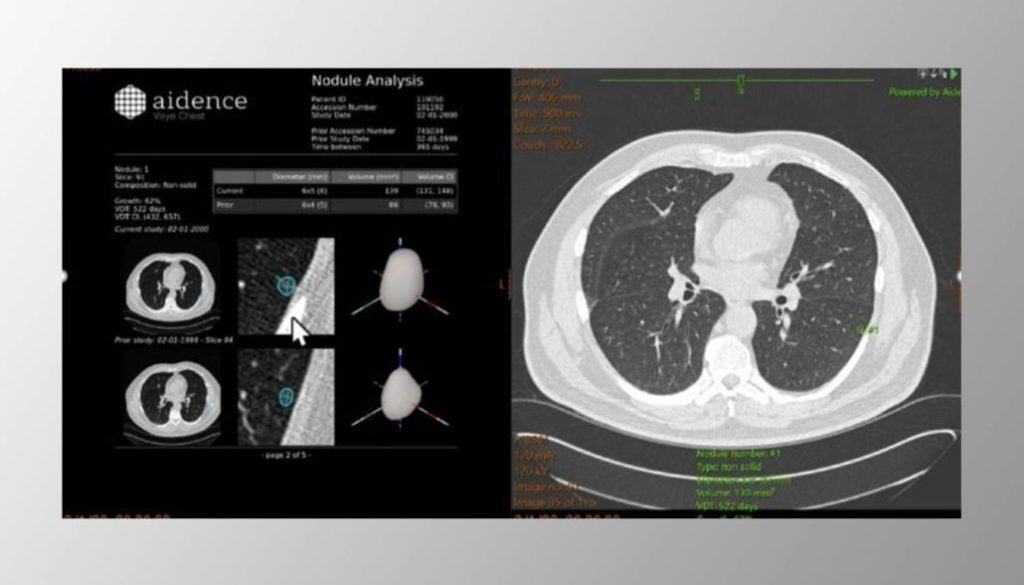

The industry-leading artificial intelligence from Aidence is supporting the TMC lung cancer screening service. Around three-quarters of lung cancer cases are diagnosed at a late stage in the UK and 10-year survival is poor (10%), but 79% is preventable (according to www.cancerresearchuk.org). The AI tool from Aidence, Veye Lung Nodules, helps identify any suspected lung nodules (even nodules as small as 3mm). This AI solution facilitates early lung cancer detection and can thus help save patients’ lives. Approximately 10,000 cases will be analysed by Aidence’s AI solution this year. It can be expected that about 10% of the patients will have a positive finding. (According to Gareth Davies, TMC UK Medical Director).

Aidence is marking a lung nodule in the images on the right (CT Thorax)

Aidence is marking a lung nodule in the images on the right (CT Thorax)